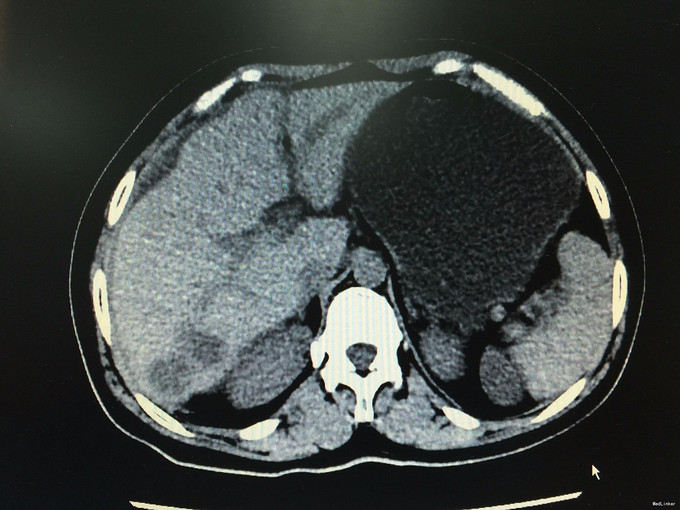

查体无特殊。辅助检查:全腹螺旋CT平扫+增强:1.考虑结肠癌,侵及肠壁全层,并盆腔、子宫直肠陷窝多发种植转移,子宫受侵,双侧附件转移,腹膜及大网膜广泛种植转移。2.肝多发转移瘤:脾门区多发结节,转移瘤可能性大。3.肝左外叶异常灌注。4.胆囊泥沙样结石,慢性胆囊炎。肠镜提示:1.直肠粘膜下隆起(囊肿?)2.内痔。进一步行肝穿刺:病理符合中分化腺癌,免疫组化提示肠癌转移可能性大。

诊断:转移性腺癌:肠癌? 排除化疗禁忌症予FOLFOX方案化疗3程。疗效评估PD。